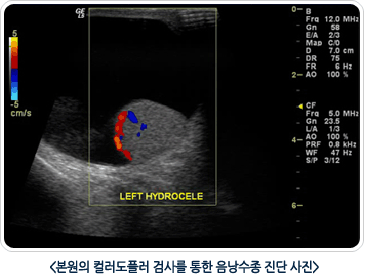

2. Ä÷¯ µµÇ÷¯ ÃÊÀ½ÆÄ °Ë»ç

À½³¶¼öÁ¾À» °¡Àå Á¤È®ÇÏ°Ô Áø´ÜÇÏ´Â ¹æ¹ýÀ¸·Î À½³¶¼öÁ¾ÀÇ ¼ºÁú, °íȯ¾ÏÀÇ À¯¹«, °íȯ ¶Ç´Â ºÎ°íȯÀÇ ÀÌ»ó À¯¹«¸¦ µ¿½Ã¿¡ È®ÀÎ ÇÒ ¼ö ÀÖ´Â Áø´Ü¹æ¹ýÀÔ´Ï´Ù.? Ä÷¯ µµÇ÷¯ ÃÊÀ½ÆÄ °Ë»ç¿Í Ç÷¾×°Ë»ç¸¦ µ¿½Ã¿¡ ½ÃÇàÇØ¼­ °íȯÁ¾¾ç¿¡ ´ëÇÑ Áø´Üµµ º´ÇàÀ» ÇÒ ¼ö ÀÖ½À´Ï´Ù.